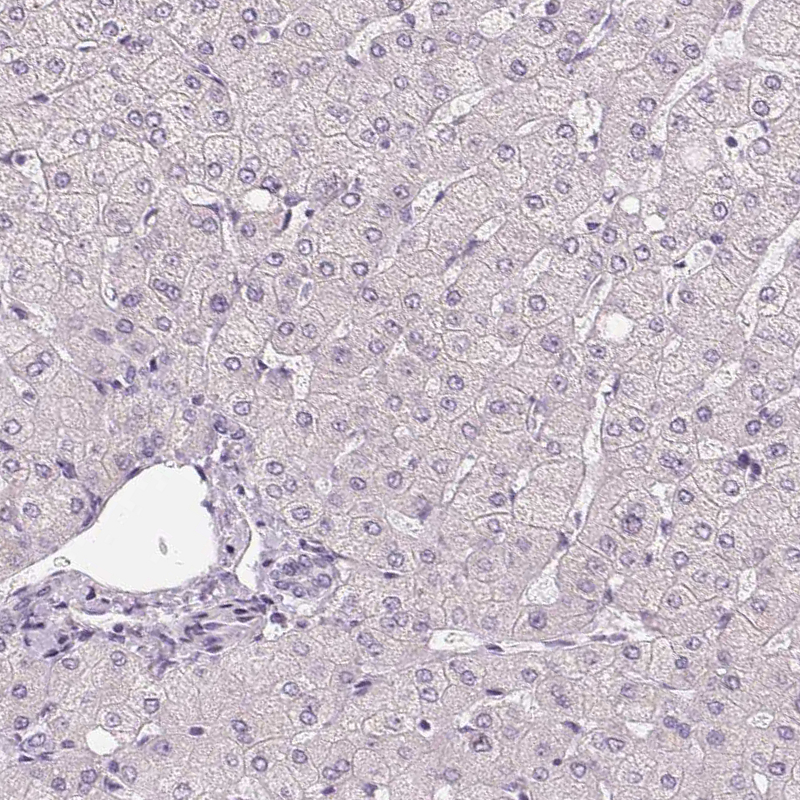

Immunohistochemistry analysis in human skin and liver tissues using HPA030180 antibody. Corresponding HOPX RNA-seq data are presented for the same tissues.